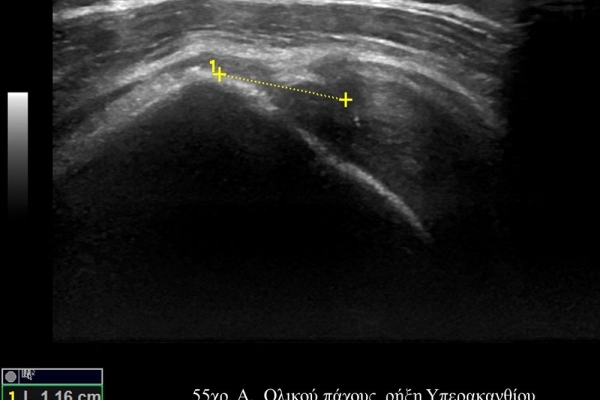

Είναι μια νέα μέθοδος που χρησιμοποιεί υψηλής ευκρίνειας υπερήχους για τη διάγνωση μυοσκελετικών παθήσεων που αφορούν τένοντες, μυς, συνδέσμους, νεύρα και περιφερικές αρθρώσεις. Η μέθοδος αναπτύχθηκε τα τελευταία χρόνια και αποτελεί αναπόσπαστο μέρος στη διαφορική διάγνωση παθήσεων που αφορούν τηνορθοπαιδική, αθλητιατρική, ρευματολογία και παιδιατρική.

Πρόκειται για υπερηχογράφημα υψηλής ευκρίνειας που επιτρέπει την λεπτομερέστατη απεικόνιση (σε επίπεδο χιλιοστού) ακόμη και πολύ μικρών/επιφανειακών ανατομικών δομών και απαιτεί ειδικό υπερηχογραφικό εξοπλισμό καθώς και εξειδίκευση του ακτινολόγου. Η εξέταση γίνεται με δυναμικό τρόπο, δηλ εκτελούνται δοκιμασίες κίνησης του μέλους που πάσχει, ώστε να αποκαλυφθεί η παθολογίαακόμη και όταν δεν είναι εμφανής σε θέση ηρεμίας. Επιπλέον, η εξέταση είναι ανώδυνη και ασφαλής και δεν περιλαμβάνει ακτινοβολία (CT), μαγνητικό πεδίο (MRI) ή παραμονή σε κλειστό χώρο και είναι πολύ ανεκτή τόσο σε ενήλικες όσο και σε παιδιά.

- Παθήσεις Ώμου (πχ ρήξη στροφικού πετάλου)